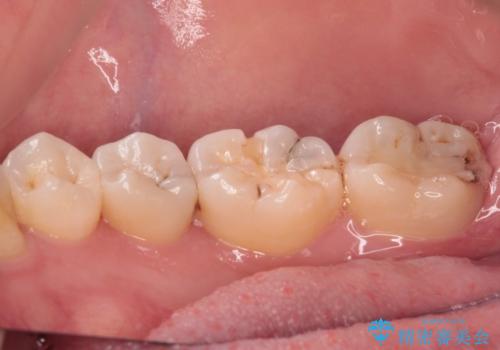

- 奥歯に頻繁に物が挟まるとのことで来院された患者様です。

最近ものが挟まりやすくなったり、冷たいものがしみるようになったりといった症状があり、診査したところ、むし歯や歯質の欠損、不適修復物などが認められました。

精度の高いセラミックインレーによる修復治療を行うこととしました。

処置を行った歯以外にもむし歯と思われる歯が多数ありますが、費用のかかる治療であれば、優先順位をつけて、処置を急ぐ歯から処置を進めて行きました。